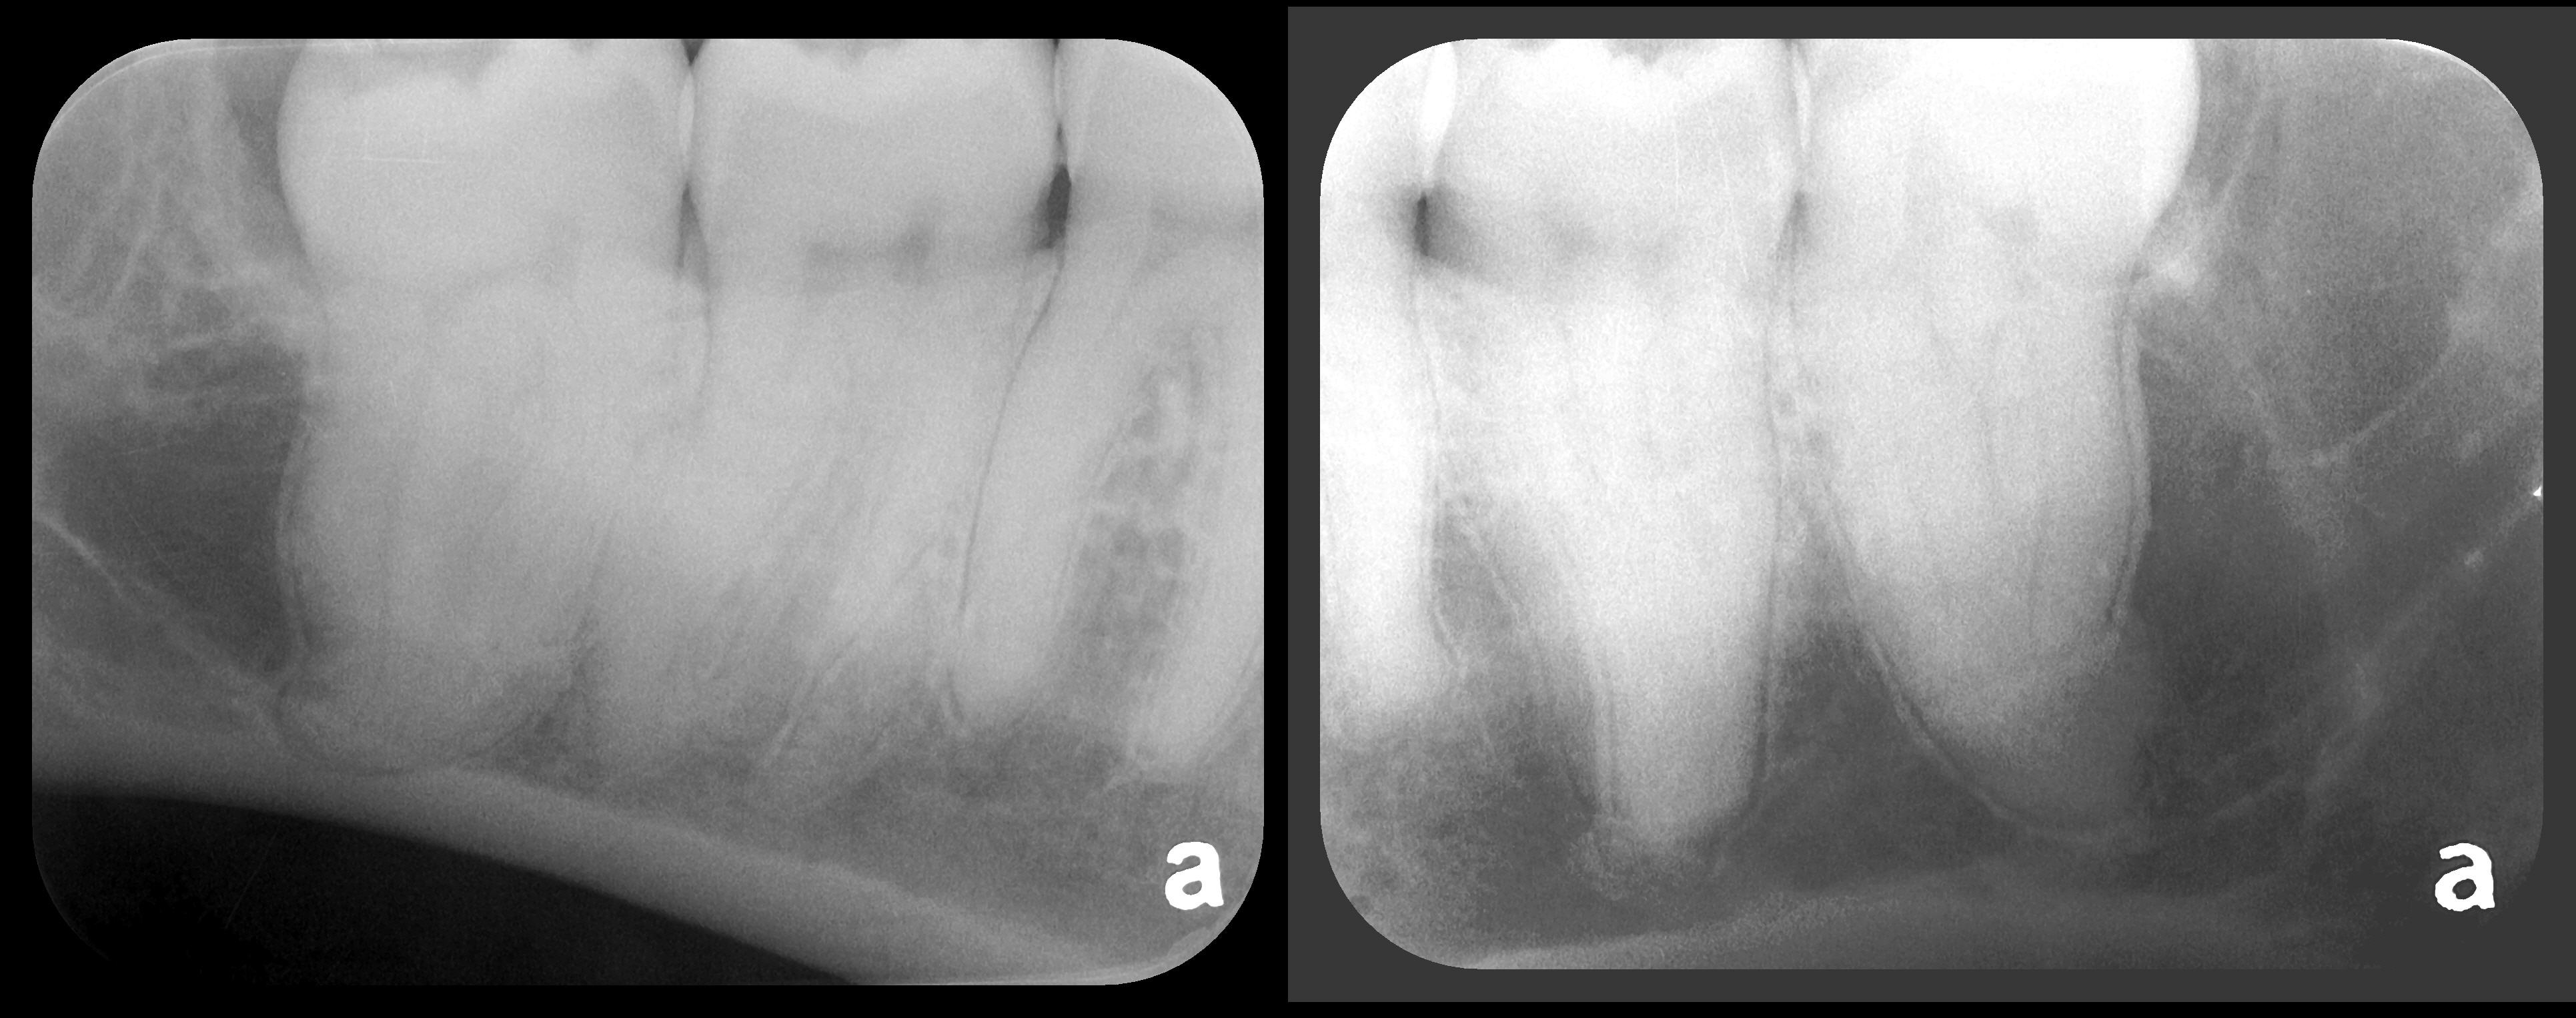

There are two specific types of DIDR sensor systems available to dentists in the marketplace: the hard-wired (HW) sensor and the photostimulable phosphor (PSP) sensor,1,2 also commonly known as phosphor "plates." A desirable feature common to both modalities is the ability to expose either bitewing (BW) or PA radiographic images. The BW radiograph (Figure 1) is usually considered more appropriate for caries detection, whereas the PA (Figure 2) is diagnostic for several different anatomic and pathologic issues.7

Fig 1. Left: Representative PSP BW radiograph with multiple restorative materials of varying radiographic densities. Tooth No. 31 demonstrates deep

caries on mesial aspect beneath the restorative. Radiolucency of carious lesion results from the low relative density of caries compared with healthy

tooth structure. Right: PSP BW radiograph optimized for view of multiple interproximal carious lesions.

Figure 1